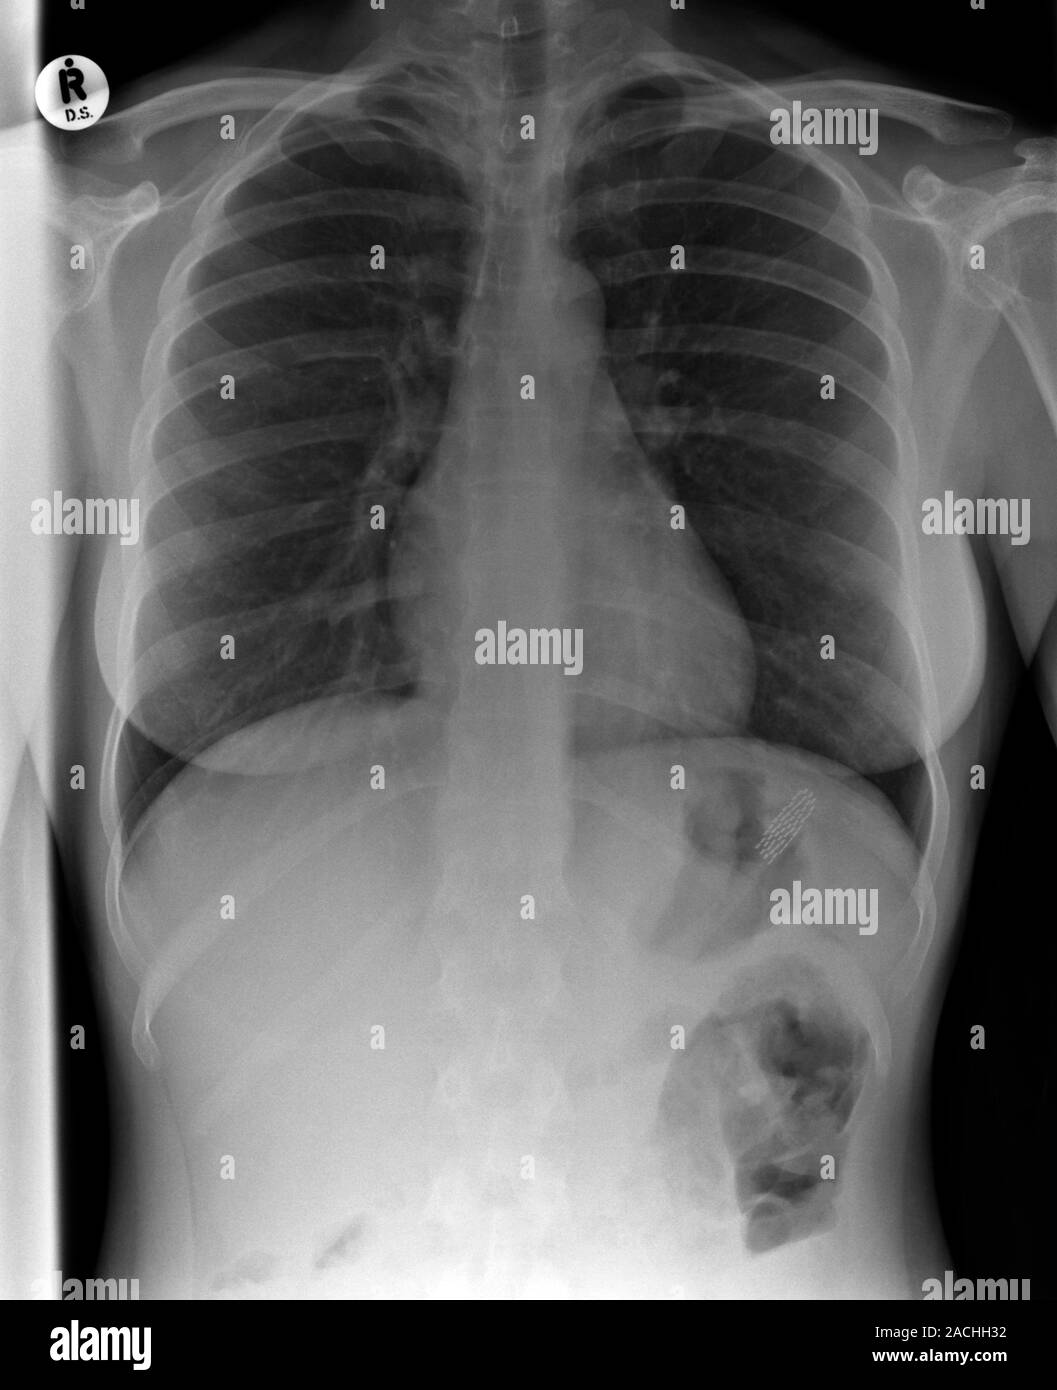

Swallowed toothbrush. Xray of the abdomen of a female patient who has Can You Swallow A Toothbrush instinctively, you swallow. a corresponding axial ct image in soft tissue window (b) reveals radiopaque bristles of stacked swallowed. in this study it was found that most cases of toothbrush ingestion were intentional (bulimia, induction of vomiting and mental. Though it’s rare, accidental swallowing of dental instruments happens — and can cause some serious complications. confronted. Can You Swallow A Toothbrush.